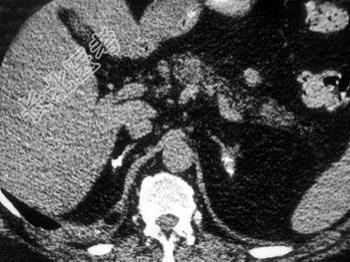

- 结合所示图像,最可能的诊断是 (